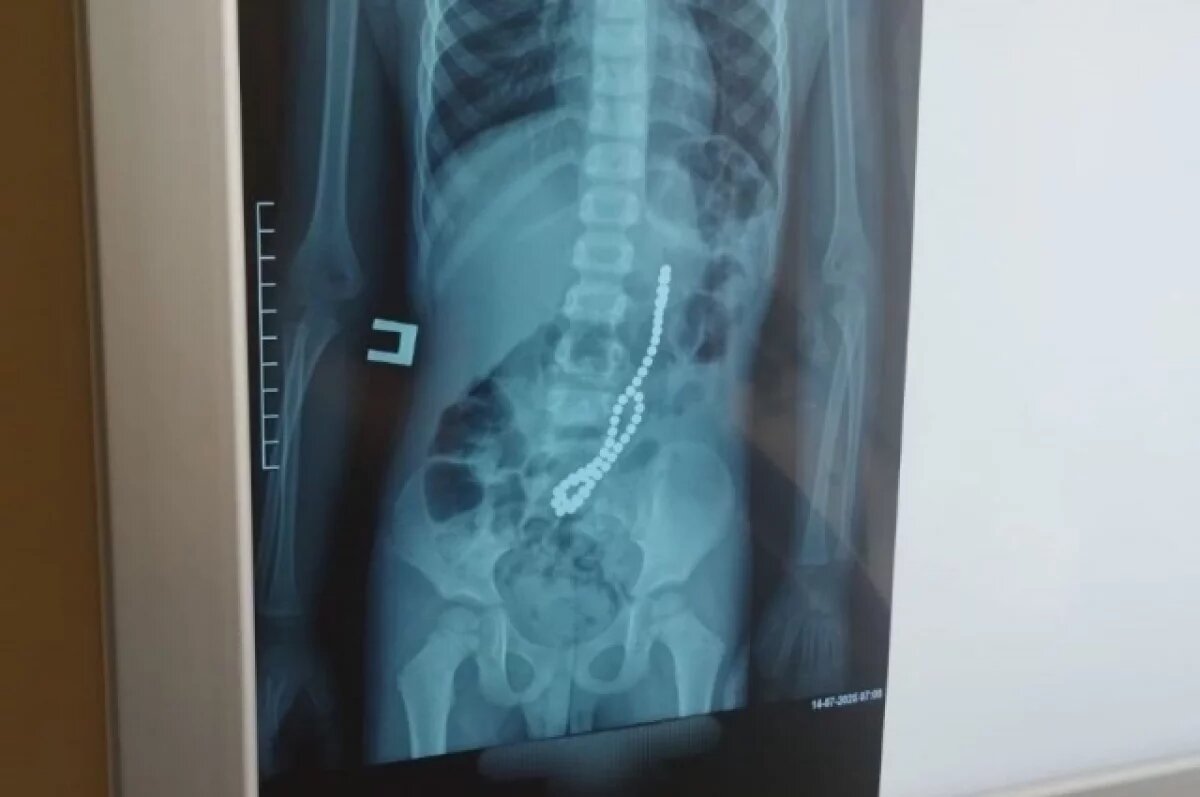

Магниты соединились в кишечнике в цепочку.

Первоначально мальчика госпитализировали в Павловскую ЦРБ с жалобами на сильные схваткообразные боли в животе. Однако врачи заподозрили, что проблема не в аппендиците, и направили ребёнка на рентген. Снимки показали множество округлых инородных тел в кишечнике, после чего мальчика срочно перевезли в барнаульскую Детскую городскую больницу №7.

Повторное обследование подтвердило, что шарики не продвигаются по пищеварительному тракту. Во время операции хирурги обнаружили, что магниты от конструктора «Неокуб» соединились через стенки кишки, создав несколько сквозных отверстий.

«Из просвета кишечника было извлечено 40 магнитных шариков, однако на снимке определялось не менее 50. Чтобы обнаружить оставшиеся инородные тела, на операционном столе выполнили рентгенографию, которая показала, что магниты располагаются ещё и в желудке», — рассказал заведующий детским хирургическим отделением ДГКБ №7 Илья Бородин.